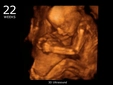

23 haftalık gebelik, hamileliğin ikinci trimesterinin sonlarına yaklaşıldığı bir dönemi ifade eder. Bu süre zarfında, hem anne hem de bebek için birçok önemli gelişim ve değişiklik yaşanmaktadır. Bu makalede, 23 haftalık gebelik dönemindeki fiziksel ve duygusal değişimlerin yanı sıra, bebeğin gelişimi, anne adayının sağlığı ve dikkat edilmesi gereken hususlar ele alınacaktır. Bebeğin Gelişimi23 haftalık gebelikte bebek, hızla büyümeye devam etmekte ve birçok önemli gelişim sürecinden geçmektedir. Bu dönemde, bebeğin gelişimiyle ilgili bazı önemli noktalar şunlardır: